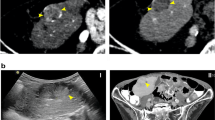

DNA from the micronodules and adjacent liver was successfully extracted in all cases. Among the 112 micronodules studied, 57 (51%) had a final ratio equal to or greater than 1.5, indicating a monoclonal pattern according to the titration curve. Representative profiles of monoclonal and polyclonal micronodules are shown in Figure 1. In all cases of cirrhosis, a mixture of mono- and polyclonal micronodular lesions was observed, with a prevalence of monoclonal nodules ranging from 25% to 71%. In all cases, topographic distribution showed a random distribution of mono- and polyclonal nodules in cirrhotic livers (Fig. 2).

Clonal analysis of microdissected liver nodules in 2 cases of cirrhosis. Upper panel, Cirrhosis Case 4: methylation patterns without digestion (top) or after HpaII digestion (bottom) of the macronodule (48) and two micronodules (53 and 44) are shown. A significant decrease of one of the alleles is observed after HpaII digestion in nodules 48 and 53, suggestive of monoclonality (M). Nodule 44 exhibits the same methylation pattern without digestion or after HpaII digestion, suggestive of polyclonality (P). Lower panel, Cirrhosis Case 7: macronodule (9) and nodule 4 are polyclonal (P) since both of them display the same methylation pattern without digestion or after HpaII digestion. Only one peak is observed after HpaII digestion in nodule 3, suggestive of monoclonality (M).

When analyzing correlations between clonal pattern and various parameters, we observed that monoclonal micronodules were significantly larger than polyclonal micronodules. Based on this observation, we can postulate that enlargement of micronodules is related to clonal expansion of a group of monoclonal liver cells rather than to the multiplication of regenerative polyclonal cells. In a previous study showing that 43% of regenerative nodules in hepatitis C virus-induced liver cirrhosis were monoclonal, it was suggested that monoclonal nodules are derived from separation by fibrous septa of larger monoclonal cell clusters (Aihara et al, 1994). Such a hypothesis would result in the juxtaposition of monoclonal nodules. By showing random distribution of poly- and monoclonal nodules within the cirrhotic liver, our study does not support such a hypothesis.